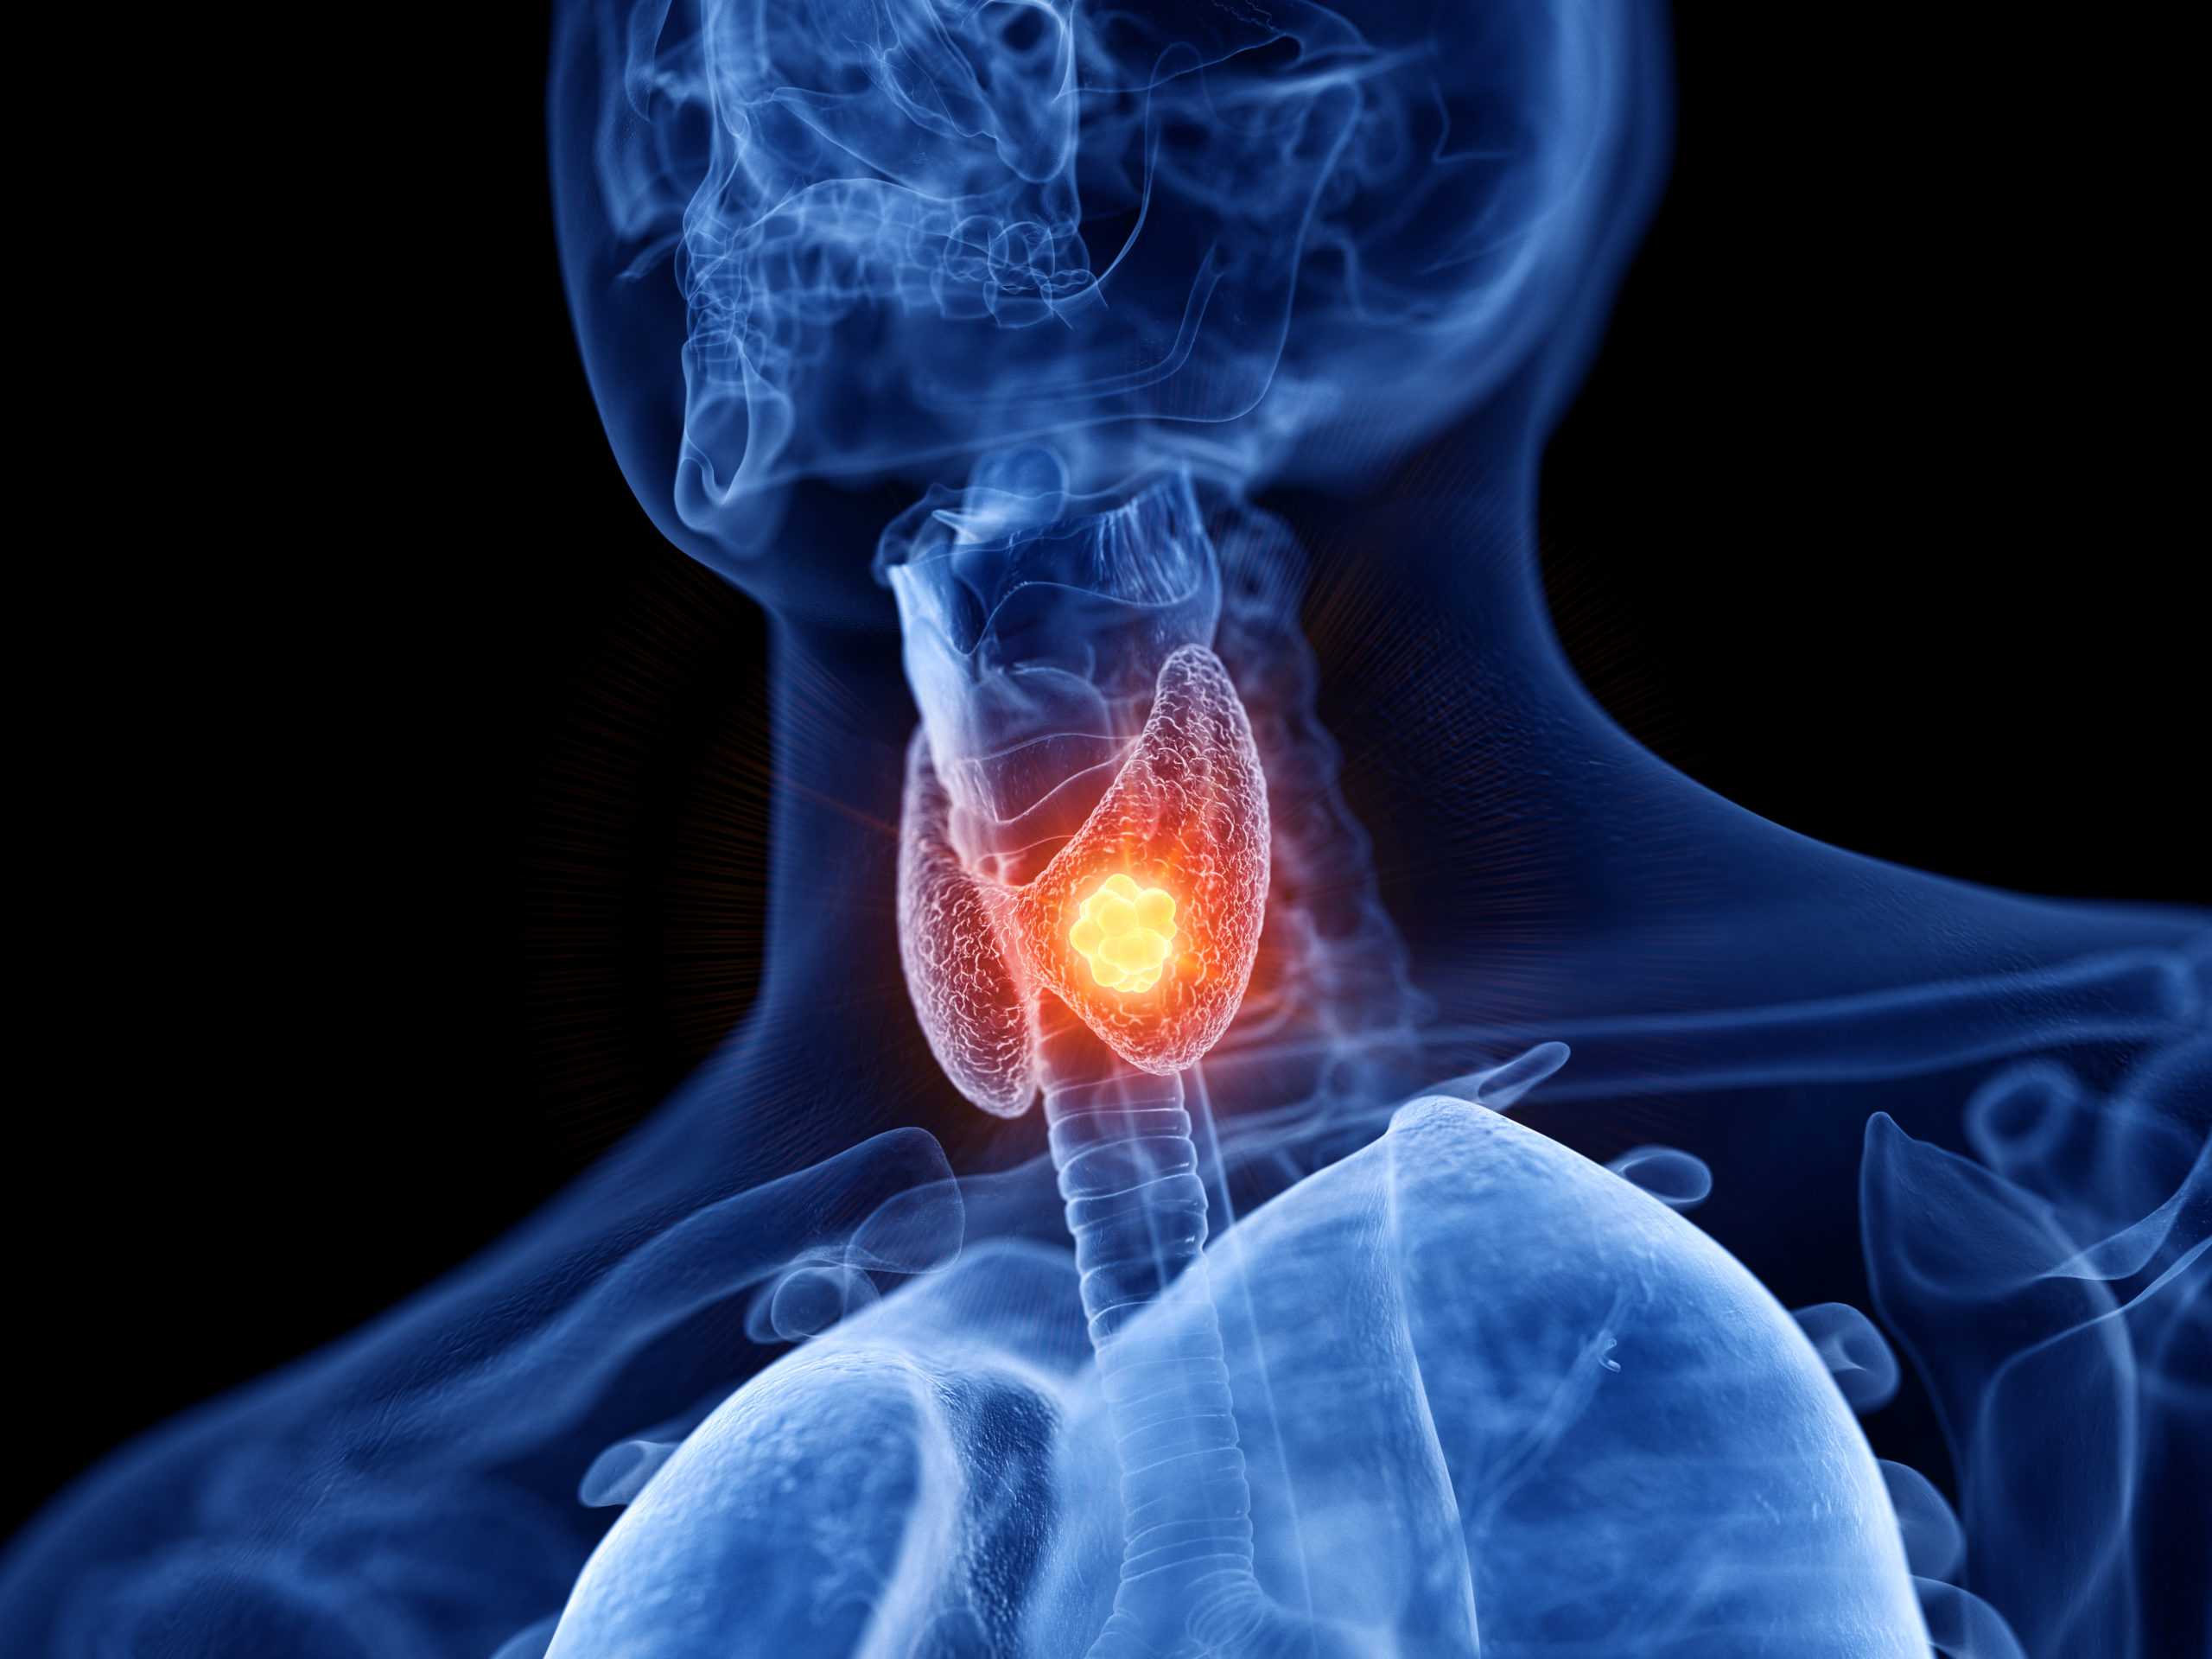

THYROID CLINIC